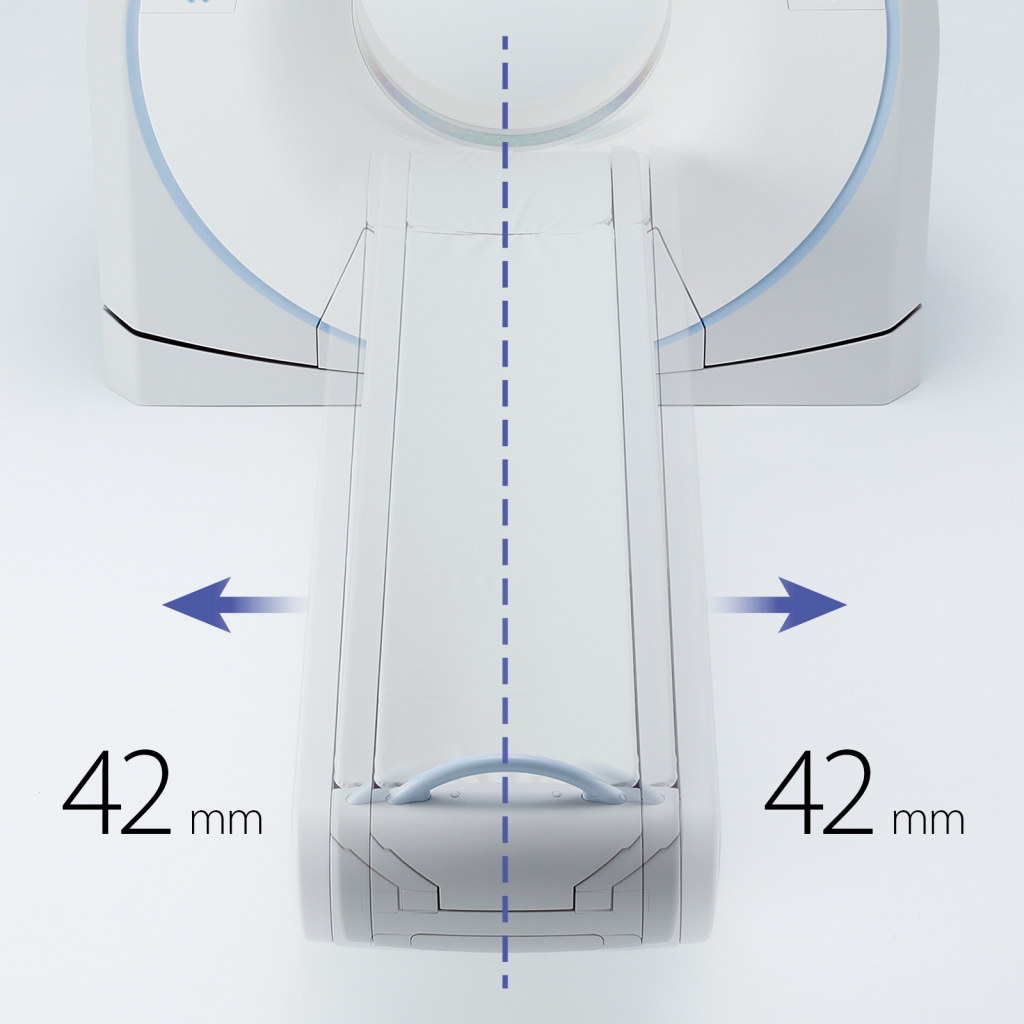

Компьютерный томограф Aquilion Lightning 80 Canon укомплектован детектором с полем охвата 20 мм, что предоставляет исследователю новые клинические возможности. Мощный генератор рентгеновских лучей, апертура гентри 780 мм и минимальная высота стола 32 см с функцией механизированного перемещения влево-вправо на 42 см предоставляют возможность проводить обследование даже очень полных пациентов. Современная рентгеновская трубка обладает существенной интенсивностью охлаждения, что позволяет осуществлять непрерывно даже самые сложные и длительные манипуляции.

Техническая помощь по боковым слайдам

Технология Assist Lateral Slide * обеспечивает безопасность и комфорт, обеспечивая моторизованное позиционирование пациента, снижая риск травмы пациента и технолога.